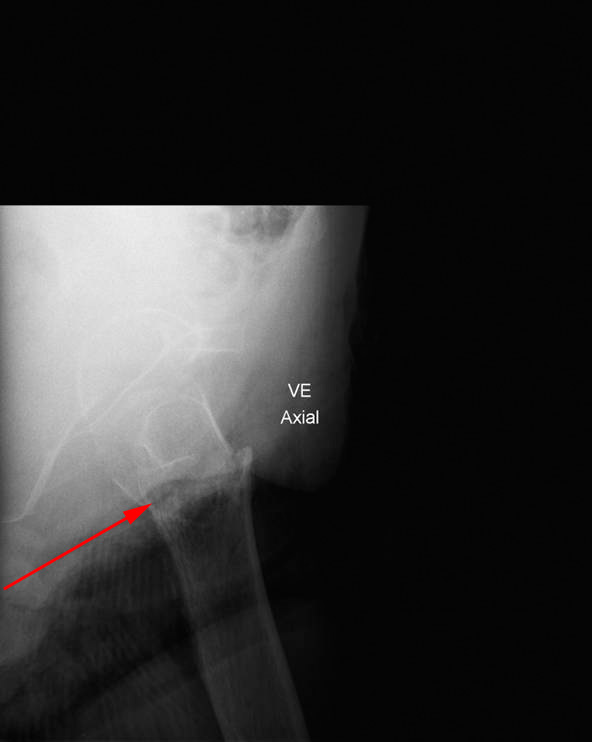

Røntgenbillede af begge hofter forfra (øverst) og enkelt billede af venstre hofte fra siden viser et brud gennem øverste del af lårbensknoglen (rød pil), kaldet hoftebrud.